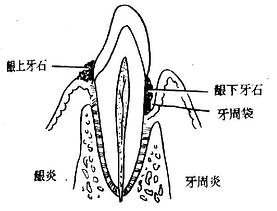

单纯性牙周炎早期应注意与边缘性龈炎的鉴别。当出现牙周脓肿时应与牙槽脓肿作鉴别(图3-13,13,表3-1)。

| 图3-12 龈炎与牙周炎的区别 | 图3-13 牙周脓肿与牙槽脓肿的鉴别 |